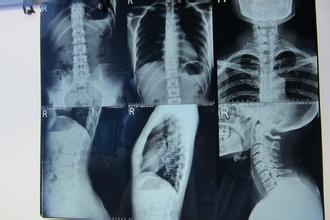

强直性脊柱炎发病症状。强直性脊柱炎的症状应该是年轻人们都需要知道的,因为生活中,强直性脊柱炎患者越来越多。那大家对强直性脊柱炎到底又了解多少呢?接下来,就让成都京研强直性脊柱炎研究院医生们来为大家分析下,强直性脊柱炎的症状到底有哪些,让大家不再对其陌生。

4、腰痛和脊柱僵硬。

下腰痛发生缓慢,钝痛状,讲不清痛在什么地方,有时牵涉至臀部。也可以疼痛很严重,集中在骶髂关节附近,放射至髂嵴、股骨大转子与股后部,一开始疼痛或为双侧,或为单侧,但几个月后都变为双侧性,并出现下腰部僵硬。晨僵是极常见的强直性脊柱炎的症状,可以持续时间长达数小时之久。长期不活动使僵硬更为明显,病人往往诉说由于僵硬与疼痛,起床十分困难,只能向侧方翻身,滚下床沿才能起立。